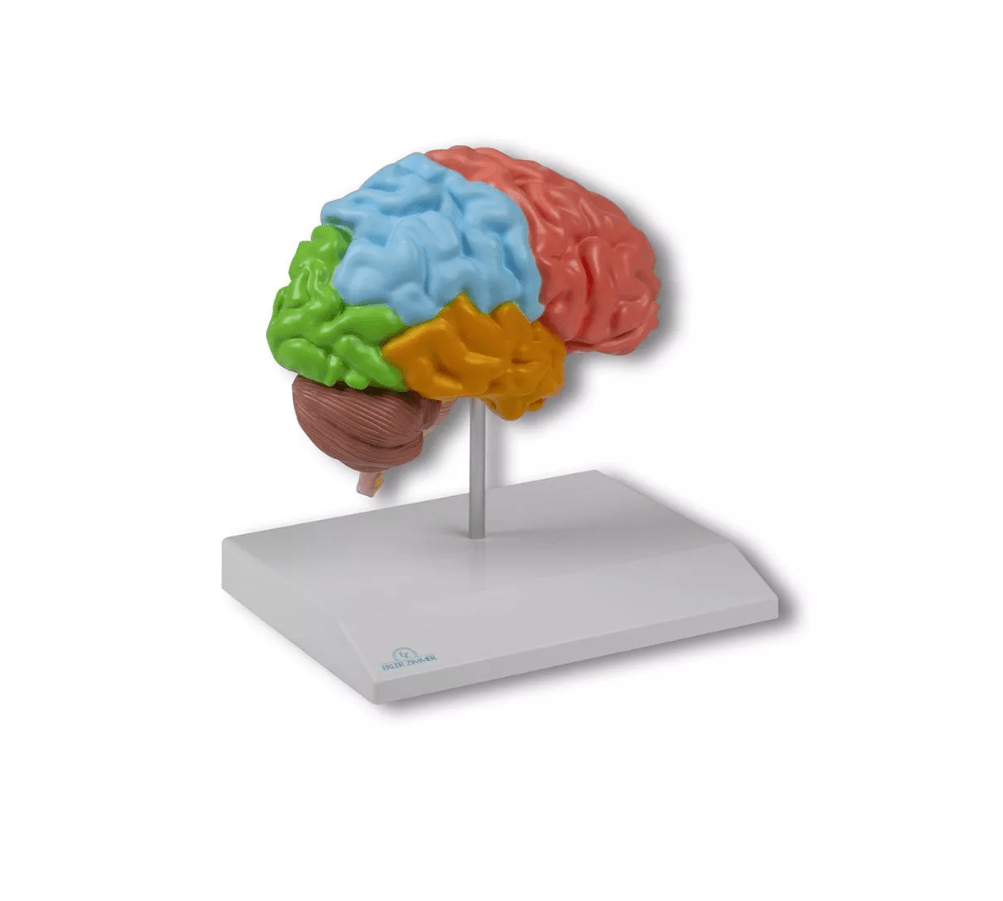

Erler-Zimmer

Gehirnhälfte, regional, lebensgroß

Artikelnummer: SKU: EZC921

PZN: PZN:

Packaging unit: VE:

Auf Lager: In 1–3 Werktagen geliefert

★★★★★ 0 Bewertungen82,59 €82,59 €82,59 € -